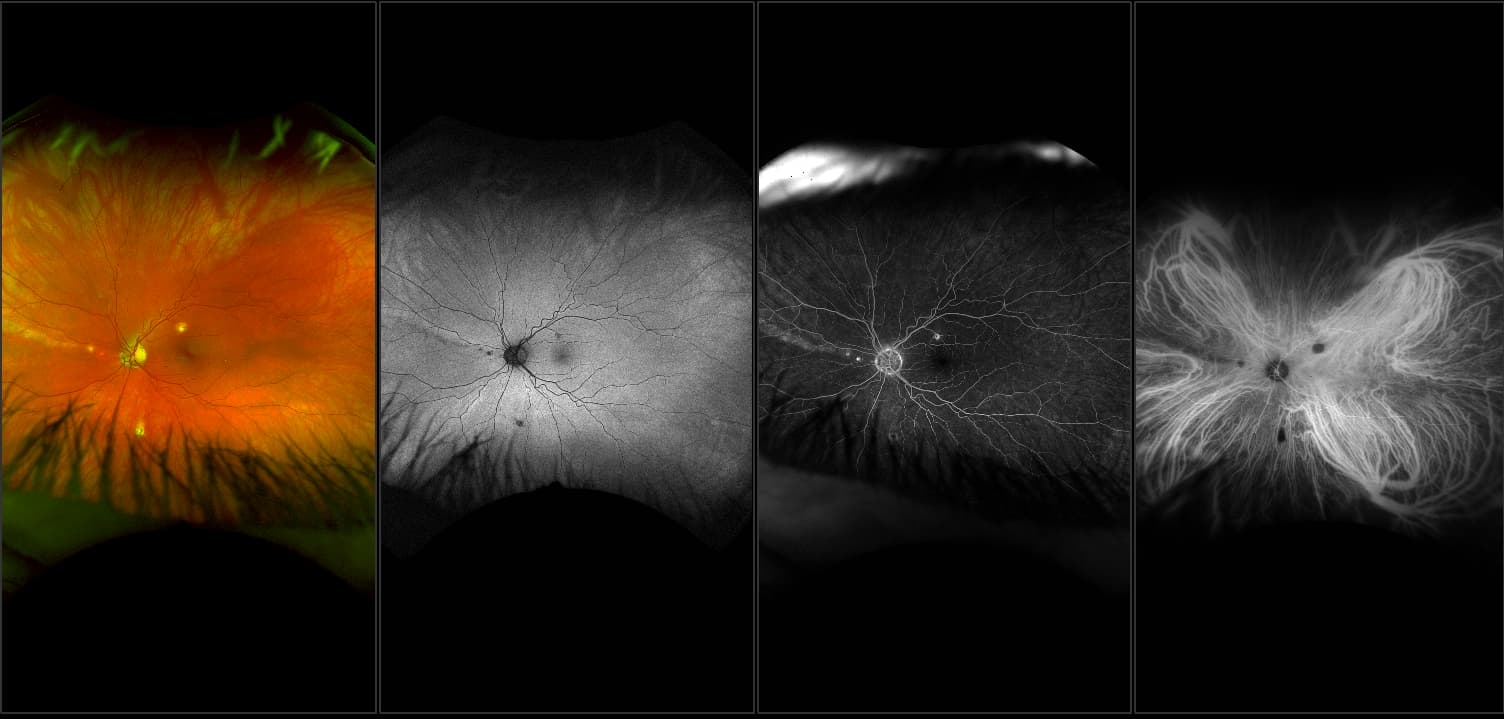

California - Large Pars Plana Cysts - Steered, RG

Pars plana cysts are a common peripheral retinal pathology that do not raise much clinical concern. They do not affect the central vision and observation alone is typically recommended. Pars plana cysts are something to be considered when peripheral retinal elevation is noted on routine exam.